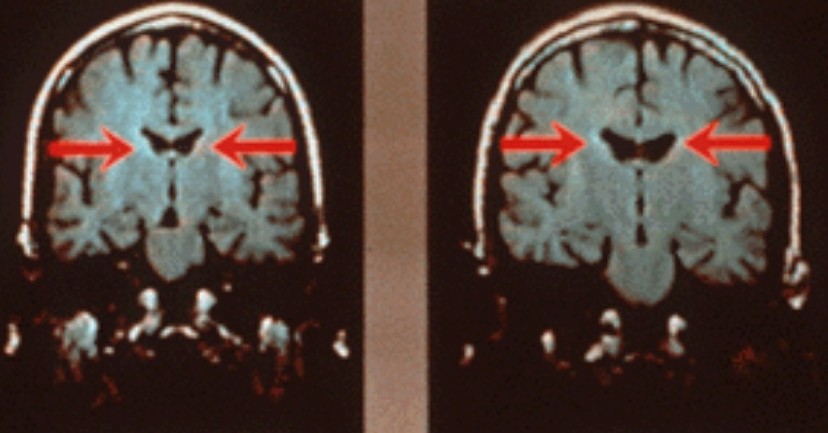

क्या आप जानते हैं कि मस्तिष्क को प्रारंभ से ही एक जीवाणु रहित वातावरण माना गया है। ऐसा माना जाता है कि रक्त-मस्तिष्क बाधा नामक एक चयनात्मक फ़िल्टर, रक्त से मस्तिष्क तक विशिष्ट जैविक पदार्थों, जैसे विषाक्त यौगिकों और जीवाणुओं के प्रसार को रोकता है। लेकिन हाल ही में सैन डिएगो (SanDiego) में 2018 सोसायटी फॉर न्यूरोसाइंस सम्मेलन (Society for Neuroscience Conference) मे अलबामा विश्वविद्यालय के वैज्ञानिकों के एक समूह ने स्वस्थ लोगों के मस्तिष्क के ऊतकों में बैक्टीरिया की उपस्थिति का सुझाव देते हुए जानकारी प्रस्तुत की ।

रोजालिंडा रॉबर्ट (Rosalinda Robert) और उनके समूह द्वारा आमतौर पर हाल ही में मृतक सिज़ोफ्रेनिया रोगियों (Schizophrenia Patients) और स्वस्थ व्यक्तियों के दिमाग के बीच अंतर का अध्ययन किया गया । अपनी जांच के लक्ष्य से अलग, वे सिज़ोफ्रेनिया रोगियों और स्वस्थ व्यक्तियों, दोनों के दिमाग में बैक्टीरिया पाकर हैरान थे। दिलचस्प बात यह है कि अधिकांश बैक्टीरिया तीन प्रकार के होते हैं जो आमतौर पर आंत में पाए जाते हैं।

बाल्टीमोर में जॉन्स हॉपकिंस सेंटर फॉर हेल्थ सिक्योरिटी (Johns Hopkins Center for Health Security in Baltimore) के एक वरिष्ठ विद्वान डॉ. अमेश अदल्जा ( Dr. Amesh Adalja) के अनुसार "मस्तिष्क को हमेशा एक जीवाणु रहित क्षेत्र के रूप में माना जाता है।" वास्तव में यह आश्चर्यजनक खोज आकस्मिक थी। दरसल शोधकर्ता इलेक्ट्रॉन माइक्रोस्कोपी (Electron Microscopy) नामक एक विस्तृत इमेजिंग तकनीक का उपयोग करके स्किज़ोफ्रेनिया (Schizophrenia) वाले और बिना सिज़ोफ्रेनिया वाले लोगों के दिमाग में अंतर की तलाश कर रहे थे।

लेकिन वैज्ञानिकों को छवियों में रहस्यमयी रॉड के आकार की वस्तुएं दिखाई दी । आखिरकार, शोधकर्ताओं ने कुछ सहयोगियों से इन जीवों के बारे में सलाह ली और पाया कि वे वास्तव में बैक्टीरिया थे। नए अध्ययन में, शोधकर्ताओं ने मानव मस्तिष्क के 34 पोस्टमॉर्टम विश्लेषणों से नमूनों का विश्लेषण किया और प्रत्येक मस्तिष्क में बैक्टीरिया पाया। महत्वपूर्ण रूप से, शोधकर्ताओं ने जांच की दिमाग में सूजन या जीवाणु रोग का कोई संकेत नहीं मिला। साइंस मैगजीन के अनुसार, जब शोधकर्ताओं ने जीवाणुओं से आनुवंशिक सामग्री का अनुक्रम किया, तो उन्होंने पाया कि अधिकांश रोगाणु जीवाणुओं के समूह से थे जो आमतौर पर मानव आंत में पाए जाते हैं,और जिन्हें फर्मिक्यूट्स, प्रोटोबैक्टीरिया और बैक्टेरोएडेट्स (Firmicutes, Proteobacteria and Bacteroidetes) के रूप में जाना जाता है।

इस संबंध में शोधकर्ताओं ने चूहों के मस्तिष्क का भी विश्लेषण किया जो मृत्यु के तुरंत बाद संरक्षित किए गए थे। सार के अनुसार, वैज्ञानिकों ने चूहे के मस्तिष्क में भी "प्रचुर मात्रा में बैक्टीरिया" को पाया, और बैक्टीरिया मानव मस्तिष्क के समान स्थानों में ही थे। निष्कर्ष इस संभावना को बढ़ाते हैं कि, मानव आंत की तरह, मस्तिष्क में भी "माइक्रोबायोम" हो सकते है। पिछले अध्ययनों ने सुझाव दिया है कि आंत में बैक्टीरिया अप्रत्यक्ष रूप से मस्तिष्क को प्रभावित कर सकते हैं।